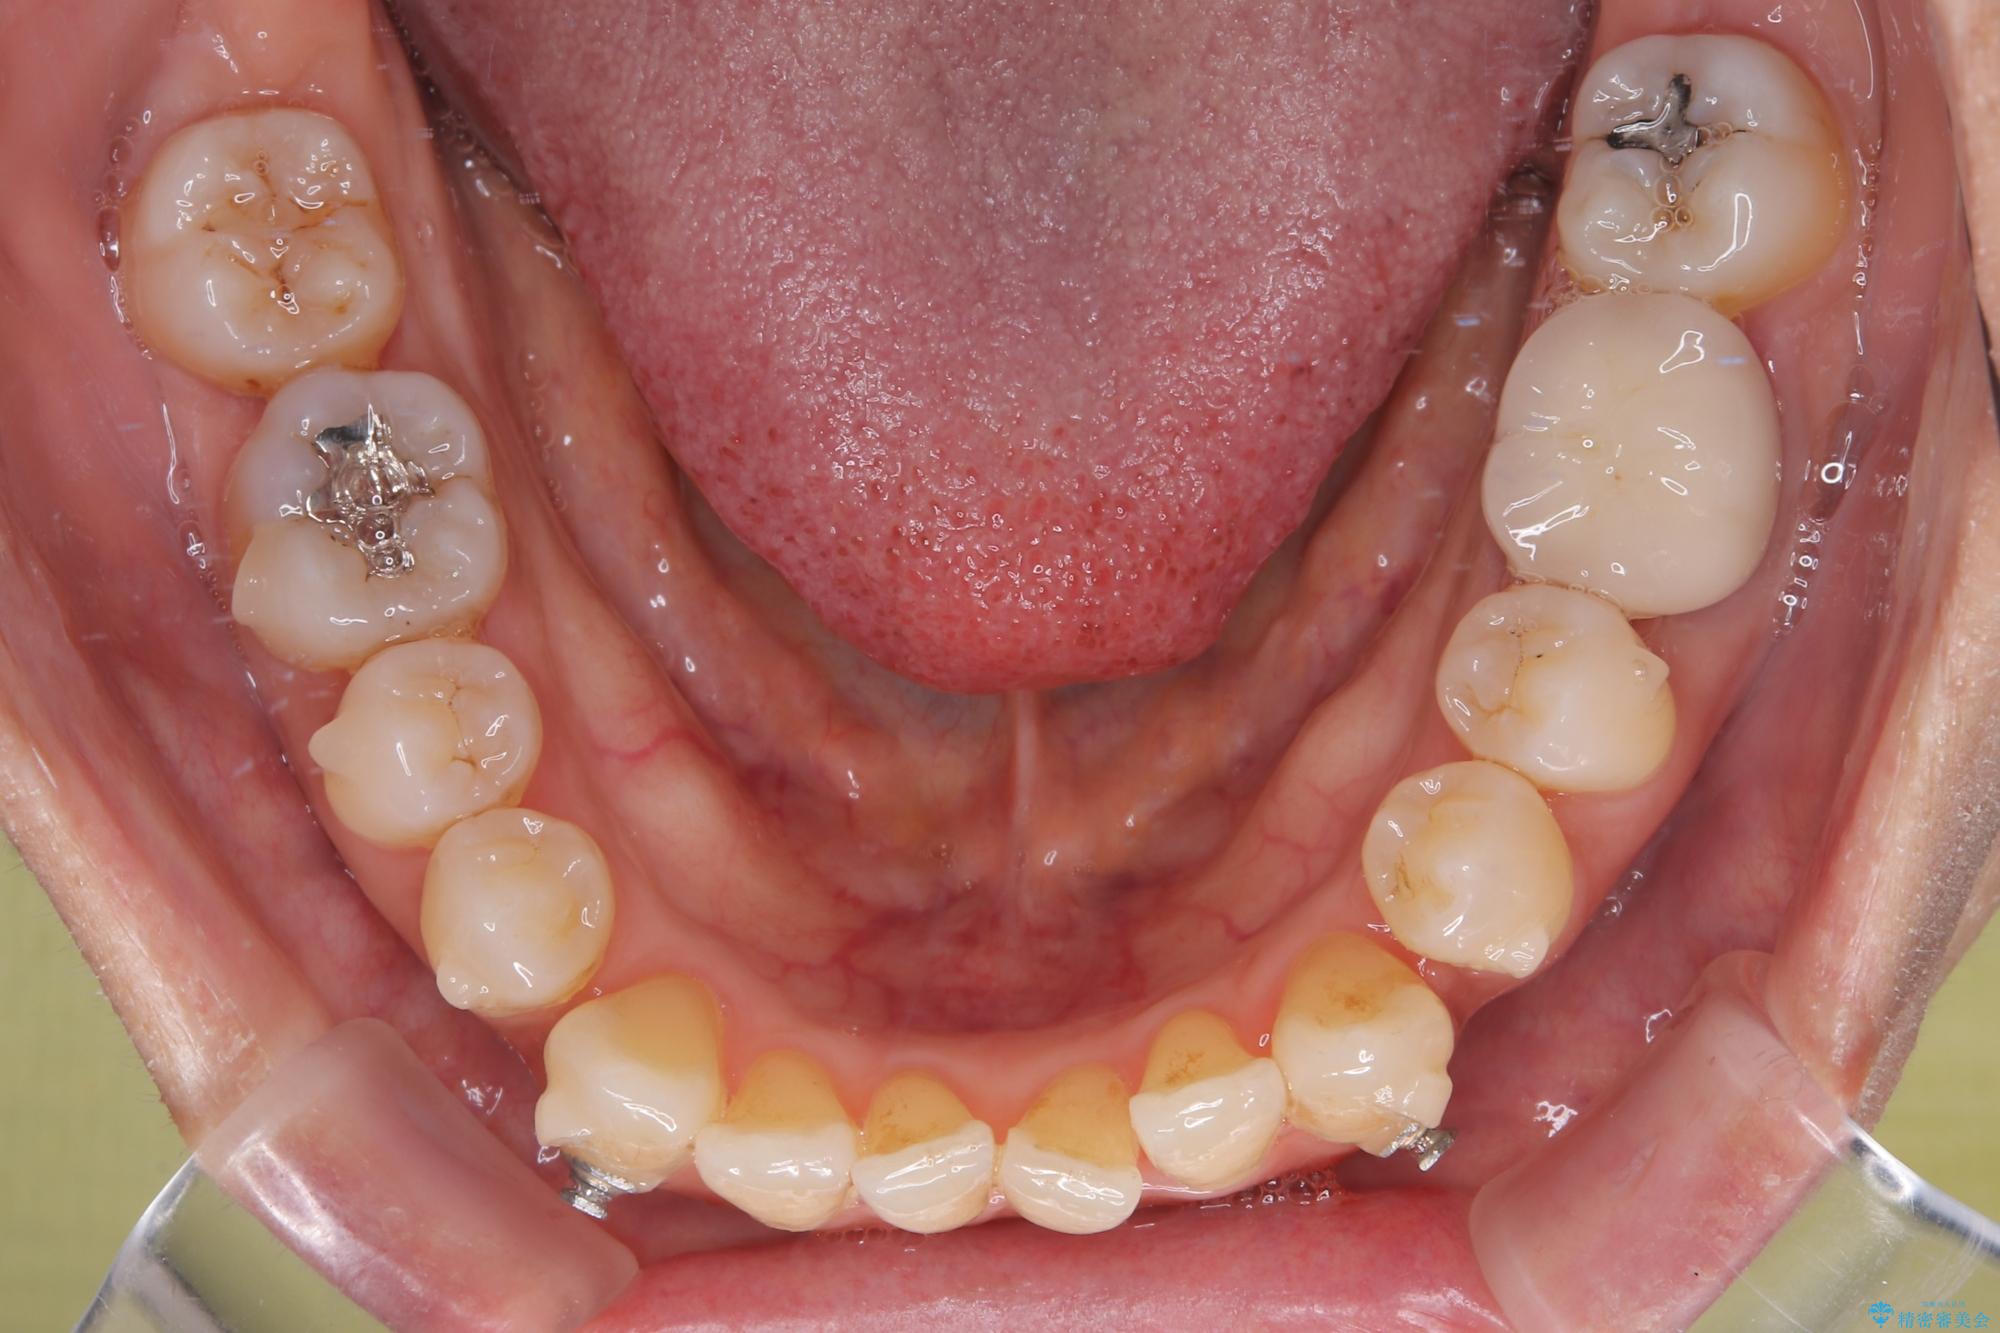

受け口と八重歯を改善 インビザライン矯正治療

- 前歯のデコボコや八重歯を治したいとのことで来院された患者様です。

受け口傾向の骨格であり、前歯はクロスバイトまたは切端咬合となっており、下顎を中心に歯列全体の後方移動を行い、IPR(歯と歯の間を削る)によってデコボコが解消するように設計し、インビザラインにより治療を行うこととしました。

受け口傾向のインビザライン矯正は比較的治療を行いやすいため、きれいに仕上げることができました。舌の突出癖が顕著であったため、改善のためのトレーニングをしっかりと行っていただきました。